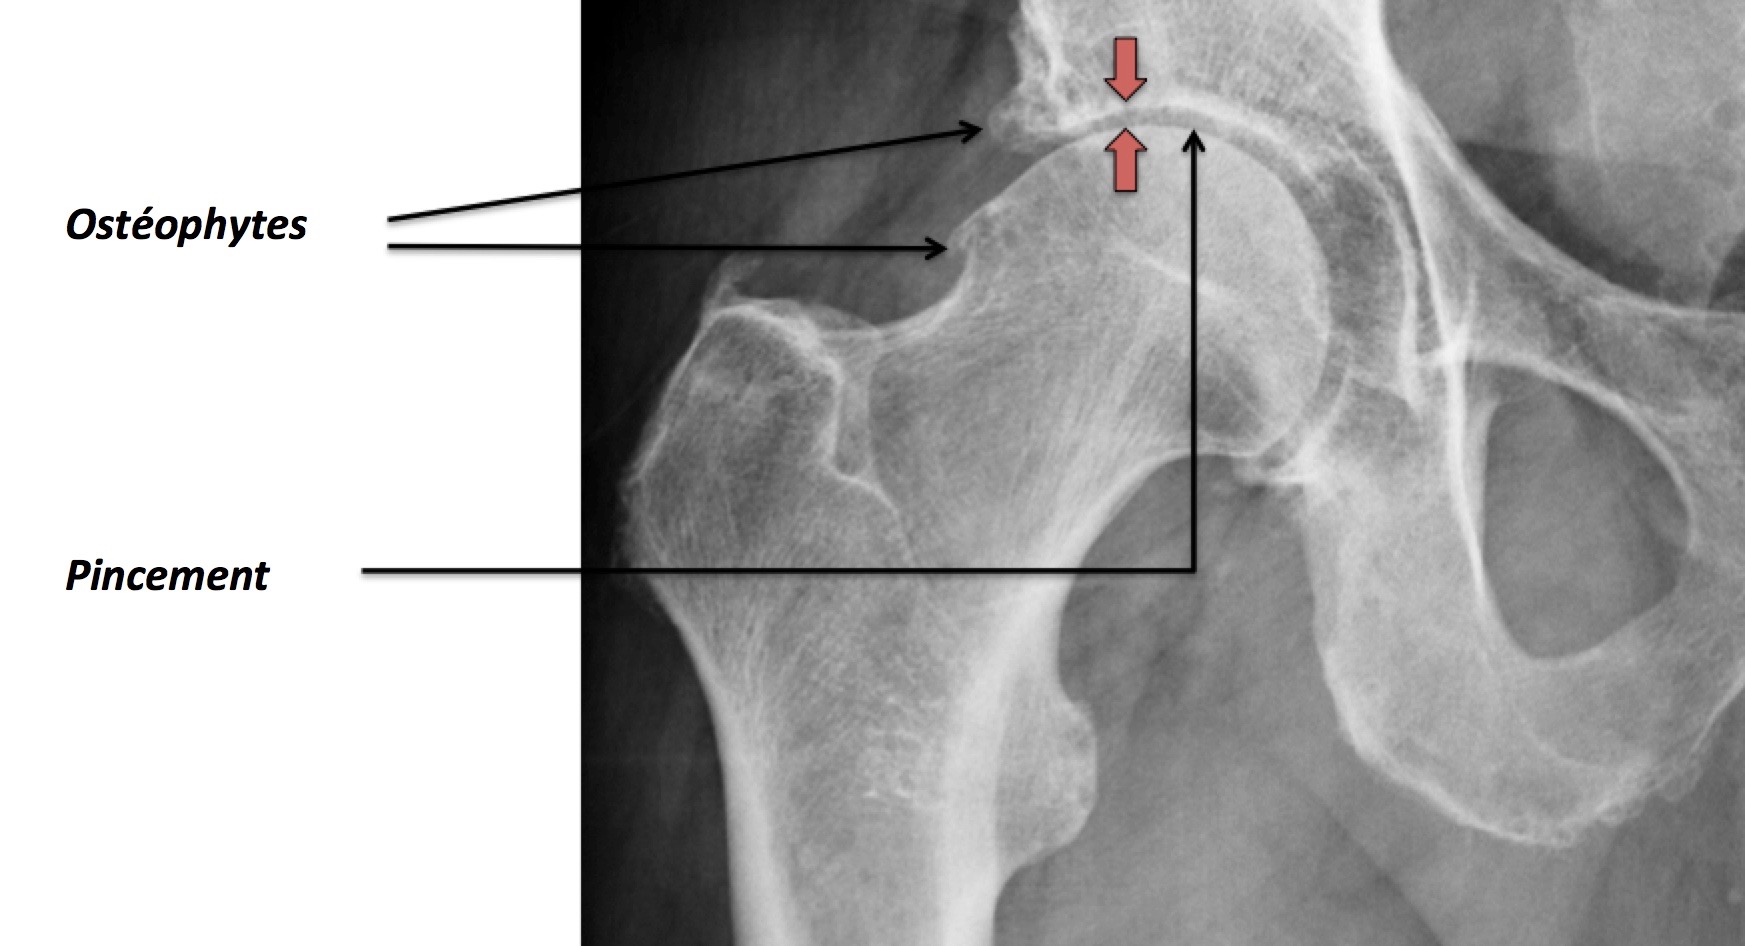

Articulation coxofémorale (Hanche)

la présence d'ostéophytes (excroissances osseuses ou « becs de perroquet ») ; la sclérose sous-chondrale (durcissement de la partie osseuse sous le cartilage) ; la déformation des extrémités osseuses (fémur, tibia, rotule). Aux premiers stades d'arthrose du genou (1 et 2), l'atteinte du cartilage est superficielle.

Arthrose de hanche ou coxarthrose Clinique Ostéo Articulaire des Cèdres Grenoble